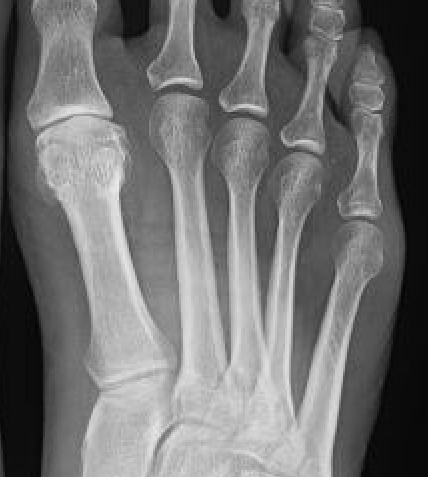

X-ray

Osteoarthritis

- joint space narrowing

- dorsomedial osteophyte

Mild to moderate OA

Severe OA